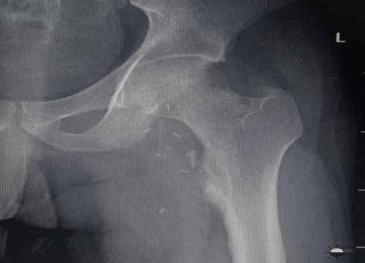

Here we report a 28 years old male present with pain in left hip and thigh due to proximal femoral Osteochondroma. Radiograph shows cauliflower-like mass originating from the left proximal femur. 3D CT scan of left thigh shows compression anterior displacement of femoral vessels near the bifurcation. This patient was treated with surgical en-bloc resection and histopathology was diagnostic of Osteochondroma.

Osteochondroma in the antero-medial aspect of subtrochanteric region of the left femur with origin abutting the lesser trochanter with a large cartilaginous cap causing compression anterior displacement of femoral vessels near the bifurcation.

Pre op X-Ray

Preop X-Ray